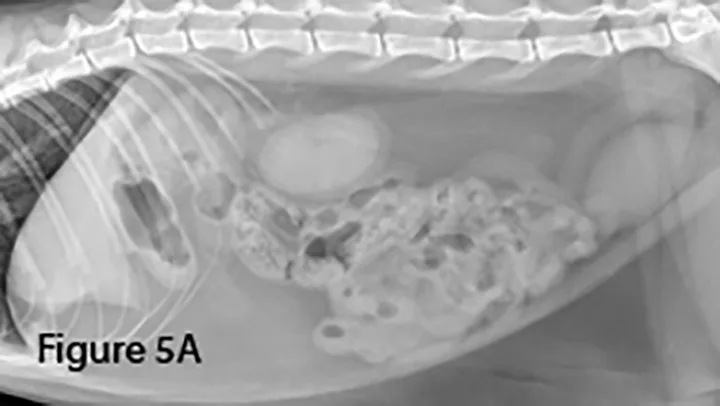

Lateral (Figure 5A) and ventrodorsal (Figure 5B) abdominal radiographs of a cat with string foreign body. Note the plicated (ie, ribbon candy) shape of small intestinal segments, bunched centrally. Pockets of triangular and odd-shaped abnormal intraluminal gas are present, common with linear foreign bodies.

To differentiate normal centralized small intestine from pathologic intestinal bunching, a plastic or wooden spoon may be used to place pressure on the lateral abdomen to disperse the intestinal segments. This cat demonstrated corrugation (ie, undulating serosal margins) of a segment of small intestine, seen in some cases of linear foreign body ingestion causing intestinal plication.